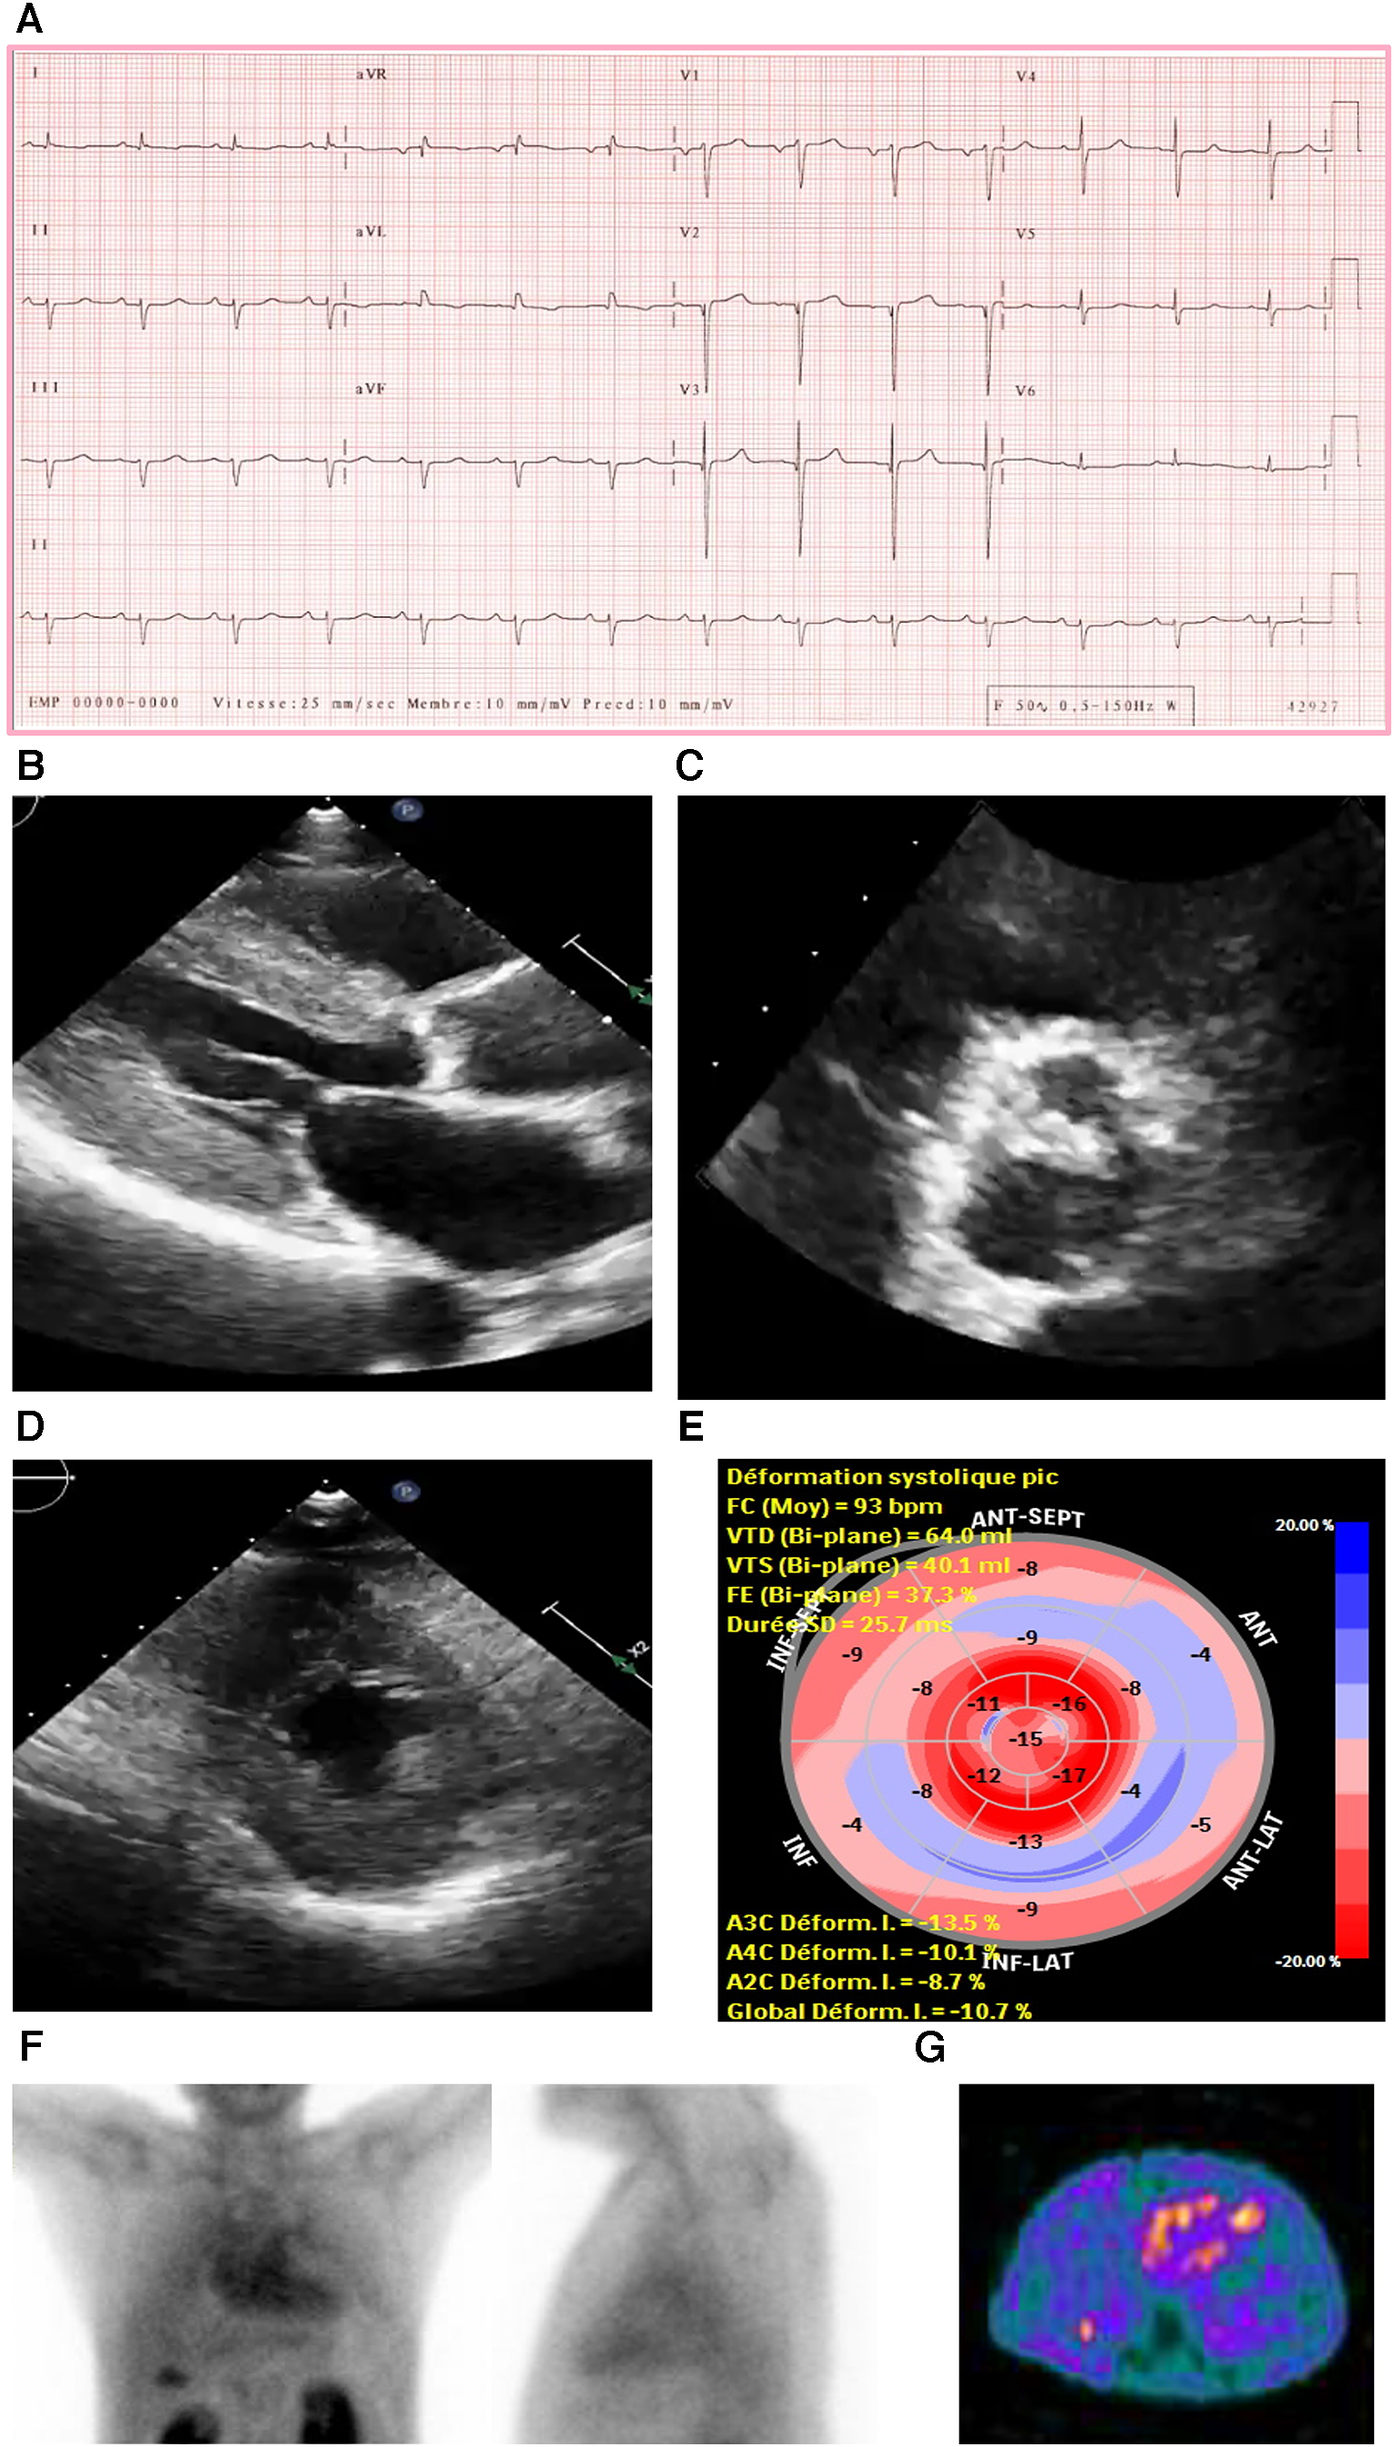

Figure 3

Case 3 clinical investigations. (A) An ECG showing regular sinus rhythm with low voltage in the limb leads and lateral leads with a prolonged PR interval (240 ms). A Q wave in v2 and v3 is noted. (B–D) A 2D echocardiography demonstrating marked concentric LV hypertrophy with severely calcified trileaflet AV causing significant AS, with low-flow and low-gradient. The EF is reduced. (E) Apical sparing with GLS reduction is seen. (F) An anterior and lateral bone scintigraphy (99mTc-PYP) scan at 1 h showing grade 3 myocardial uptake. (G) A SPECT scan demonstrating strongly positive uptake (grade 3).

AS, aortic stenosis; AV, aortic valve; ECG, electrocardiogram; EF, ejection fraction; LV, left ventricular; SPECT, Single-photon emission computerized tomography; 99mTc-PYP, technetium pyrophosphate.

An echocardiography demonstrated a small LV cavity and moderate concentric LV hypertrophy (R). There was mild to moderate global hypokinesis, with the EF calculated at 35%–40% (Figures 3B–E). The global longitudinal strain (Figure 3C) was moderately reduced and measured at −10.7% with a pattern of relative apical sparing and a ratio of basal strain segments/apical strain segments of 2. Diastolic parameters demonstrated moderate diastolic dysfunction with an E/A ratio of 1.4 consistent with a pseudo normal pattern and a moderately raised LV filling pressure. The patient exhibited a severely calcified trileaflet AV causing a significant low-flow/low-gradient AS. The SVi was 31 ml/m2, AV area was 1.09 cm2, peak gradient was 24 mmHg, and mean gradient was 14 mmHg. The patient had moderate pulmonary hypertension, and both atria were moderately dilated with high right atrial and systolic pulmonary pressure.

Due to these electrical and echocardiographic findings, there was a strong suspicion of coexistent CA in this patient with severe AS. Therefore, a bone scintigraphy of the heart was conducted (Figures 3F,G), which showed strong tracer uptake within the myocardium (grade 3) and a H/CL ratio of 2.0. A hematological workup was performed and was negative for the presence of any monoclonal component with a normal free light chain ratio, ruling out AL amyloidosis (serum and urine immunofixation test result was negative, and serum free light chain assay was in the normal range: kappa 12.5 mg/L and lambda 20.8 mg/L).